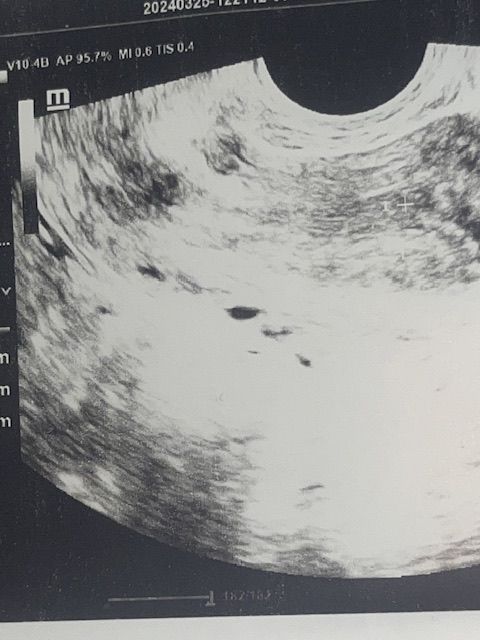

Подскажите похоже на плод?

Плод это после 13 неделе. А до эмбрион. У Вас не видно плодного яйца. Что написано в протоколе УЗИ?

Уверена, что Вам все врач написал в заключении узи, но Вы просто хотите услышать что-то, что очень ожидаете услышать. И, да, плод - это то, что идёт после эмбриона, который появляется уже после плодного яйца. Но тут нет даже его, судя по всему, увы. Если Вы думаете, что беременны, то переделайте узи через неделю.

Плод называется таковым после 8 недели беременности. До 8-эмбрион. Он виден после 5 недели беременности. До 4-5 недель он не визуализируется. До этого времени Визуализируется только плодное яйцо (темное пятно). После это выглядит как расплывчатая точка в темном круге.

Нет, это вены, матка выше, аплодное яйцо должно быть в матке , а не за ней